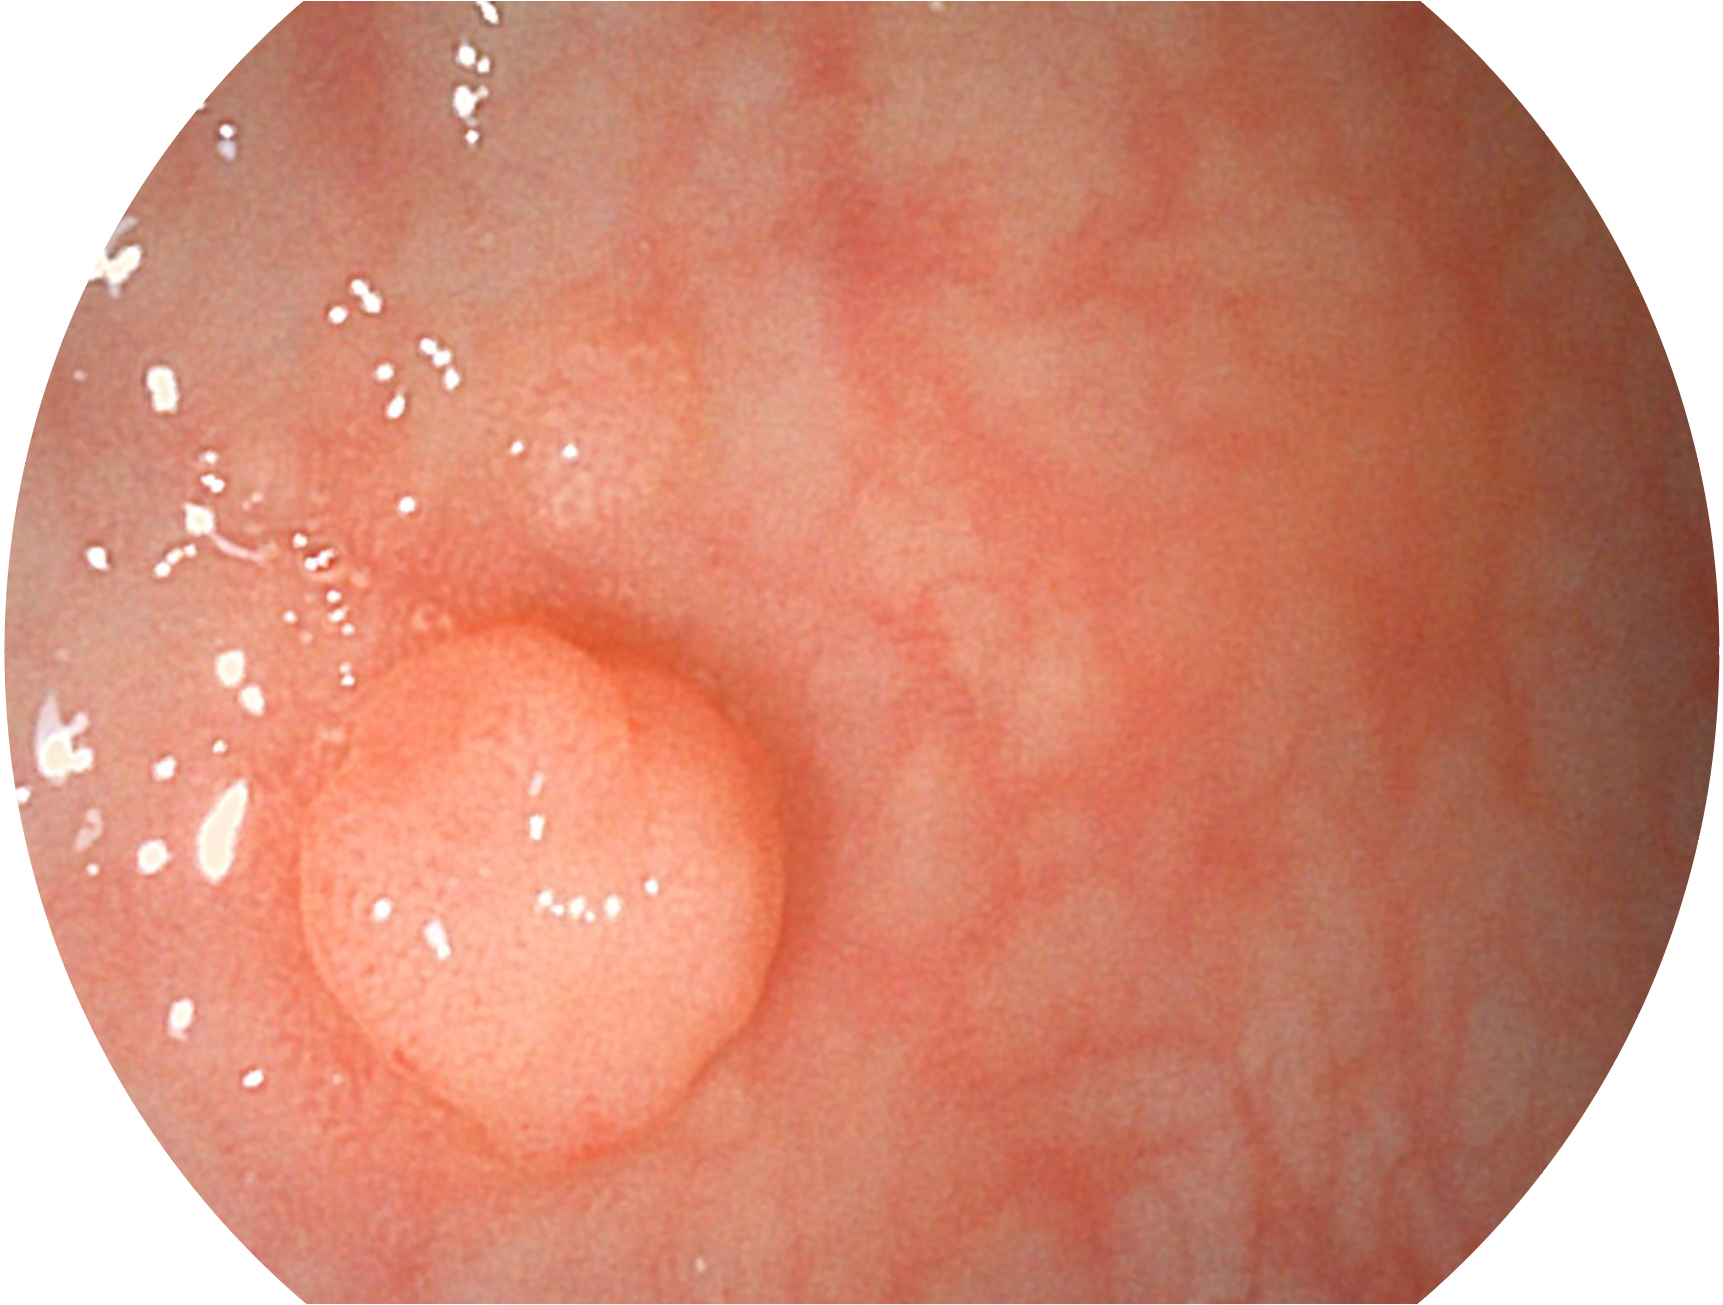

開立新開發(fā)的內(nèi)鏡染色技術(shù),主要是基于多波長LED 光源的開發(fā),VLS-55Q 四波長LED 光源是由四個(gè)不同顏色的LED光按照相應(yīng)照明模式所規(guī)定的特定發(fā)光比例進(jìn)行合束后形成,合束后形成的照明光的光譜由紅光、綠光、藍(lán)光及藍(lán)紫光這四個(gè)不同的波段范圍構(gòu)成。具有更高光譜自由度,通過光譜比例的控制,實(shí)現(xiàn)了聚譜成像技術(shù),英文全稱為“Spectral Focused Imaging, SFI”,縮寫為“SFI”和光電復(fù)合染色成像技術(shù),英文全稱為“Versatile Intelligent Staining Technology, VIST”,縮寫為“VIST”。